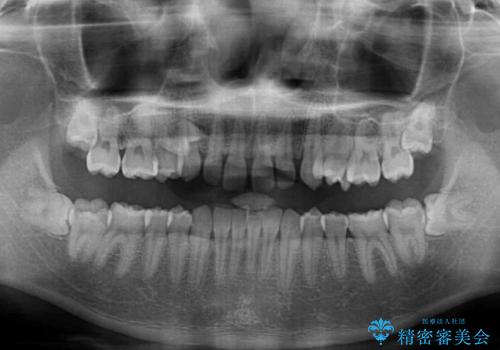

隙間の原因は、埋伏や前後に重なってしまっている上顎小臼歯と、下の前歯が見えなくなるくらいのディープバイトで、それらを改善する必要がありました。

アンカースクリューを用いて下に位置している上顎前歯を持ち上げるとともに、ワイヤー装置によりディープバイトの原因である奥歯の傾斜を改善することで、矯正治療を行っていくこととしました。

また、矯正治療に際し、4本全ての親知らずと、埋もれている右上小臼歯を事前に抜去することとしました。